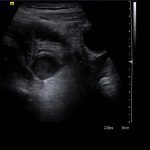

- Tubular, blind-ending structure in the right lower quadrant measuring 9 mm in diameter, which is noncompressible with mild wall thickening and mild mural hyperemia

Dilated appendix, measuring 9 mm in diameter, which is noncompressible with mild wall thickening and mild mural hyperemia, concerning for acute appendicitis.